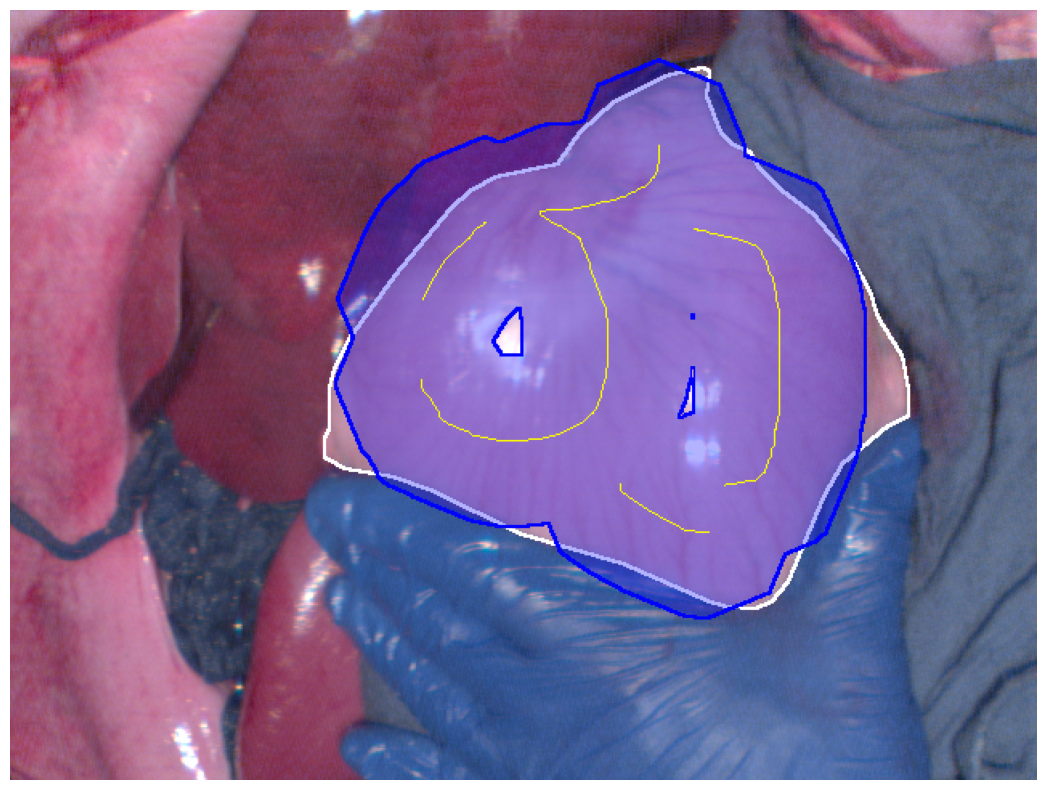

(c) Reconstructed RGB best Dice segmentation result

Figure 2: Segmentation results (blue regions) at the best Dice coefficient for different methods and ground truth (white regions), along with the curves of Dice coefficient variation with threshold adjustments.

In Fig. 2, the segmentation results at the best Dice for the four different methods are displayed, along with the variation in Dice coefficients with threshold adjustments. From Fig. 2e, it can be seen that the Euclidean distance method has the lowest maximum Dice score of 0.914. The methods using geodesic distance maps generated from hyperspectral images and reconstructed RGB images achieve similar maximum Dice values, both higher than the Euclidean method. The deep learning-based feature geodesic distance map method achieves the highest maximum dice coefficient.